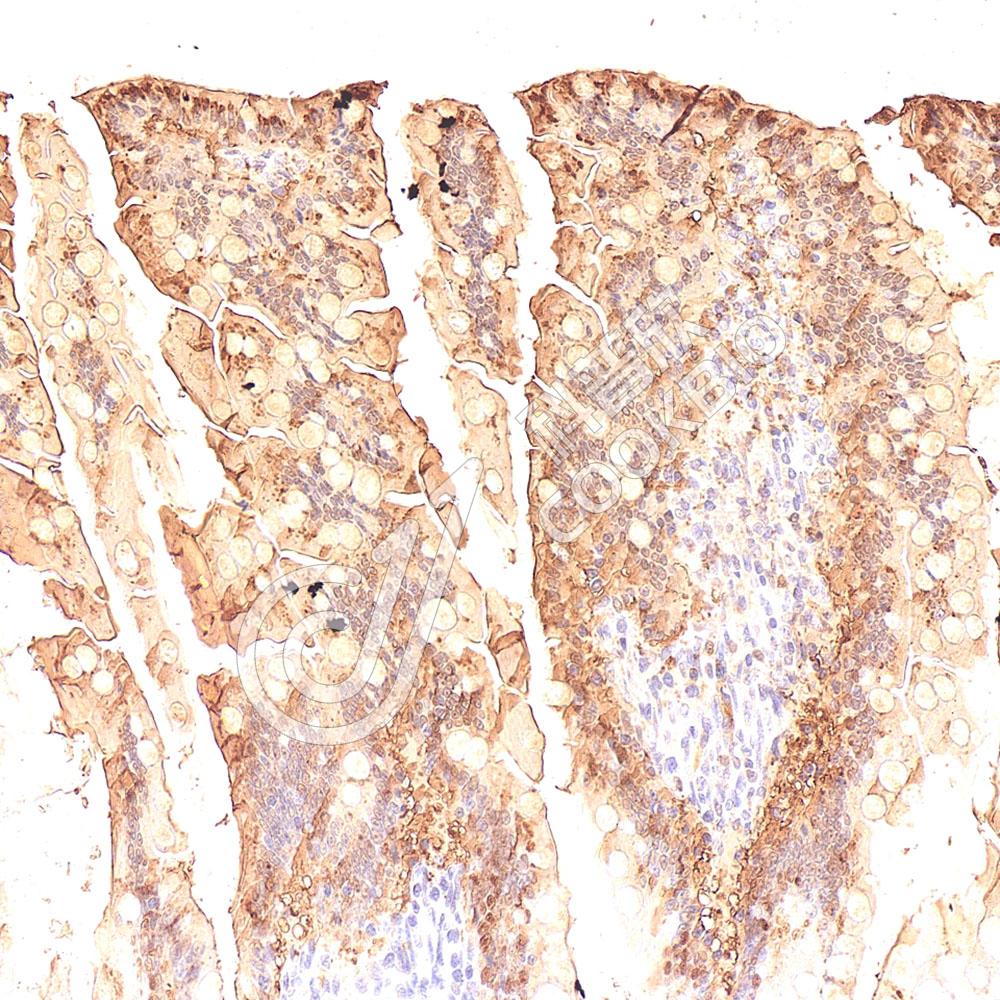

IHC检测I-FABP蛋白(货号 K1346752).

样品: 大鼠小肠, 4%多聚甲醛 (货号KSG1101) 固定12-24小时.

抗原修复: Tris-EDTA抗原修复液(pH 9.0) (KSG1203), 98℃, 20分钟.

—抗: 1: 400稀释, 4℃ 孵育过夜.

二抗: S-vision免疫组化多聚二抗(山羊抗兔),即用型 (货号KB3906), 室温孵育20分钟.